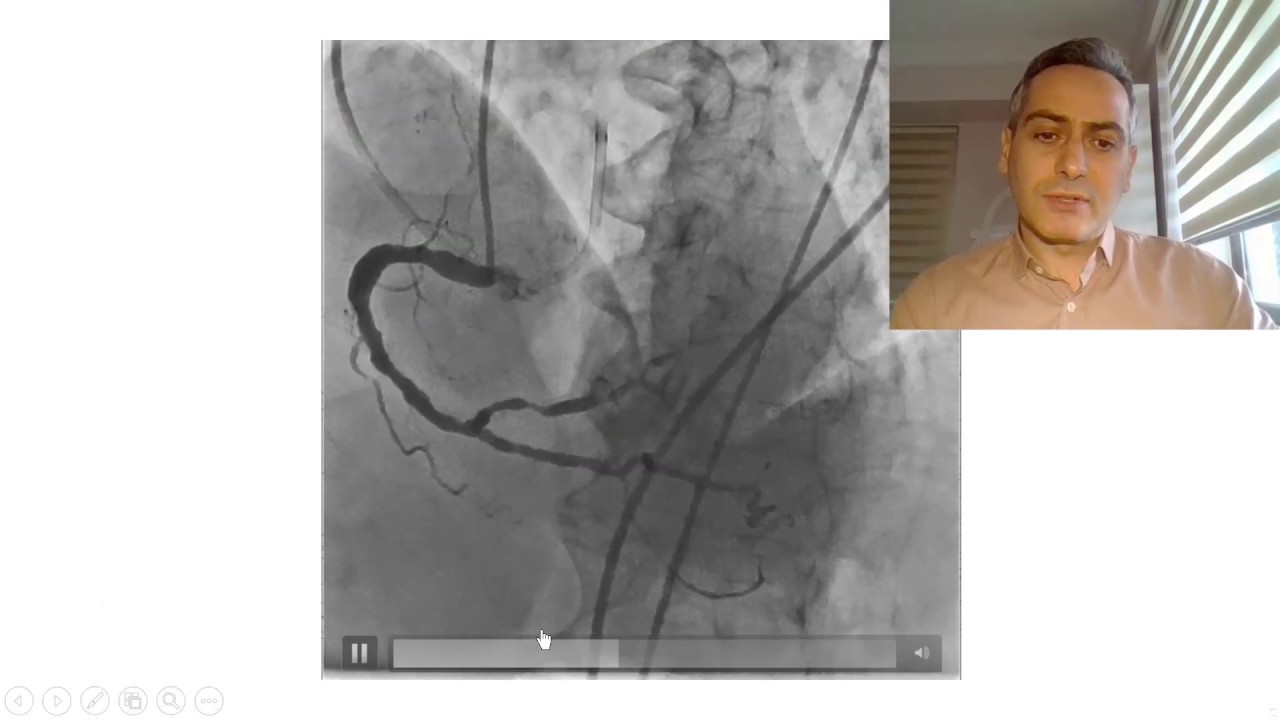

Kalp damar tıkanıklığı tedavisinde İlaç kaplı stent mi, ilaç kaplı balon mu ?